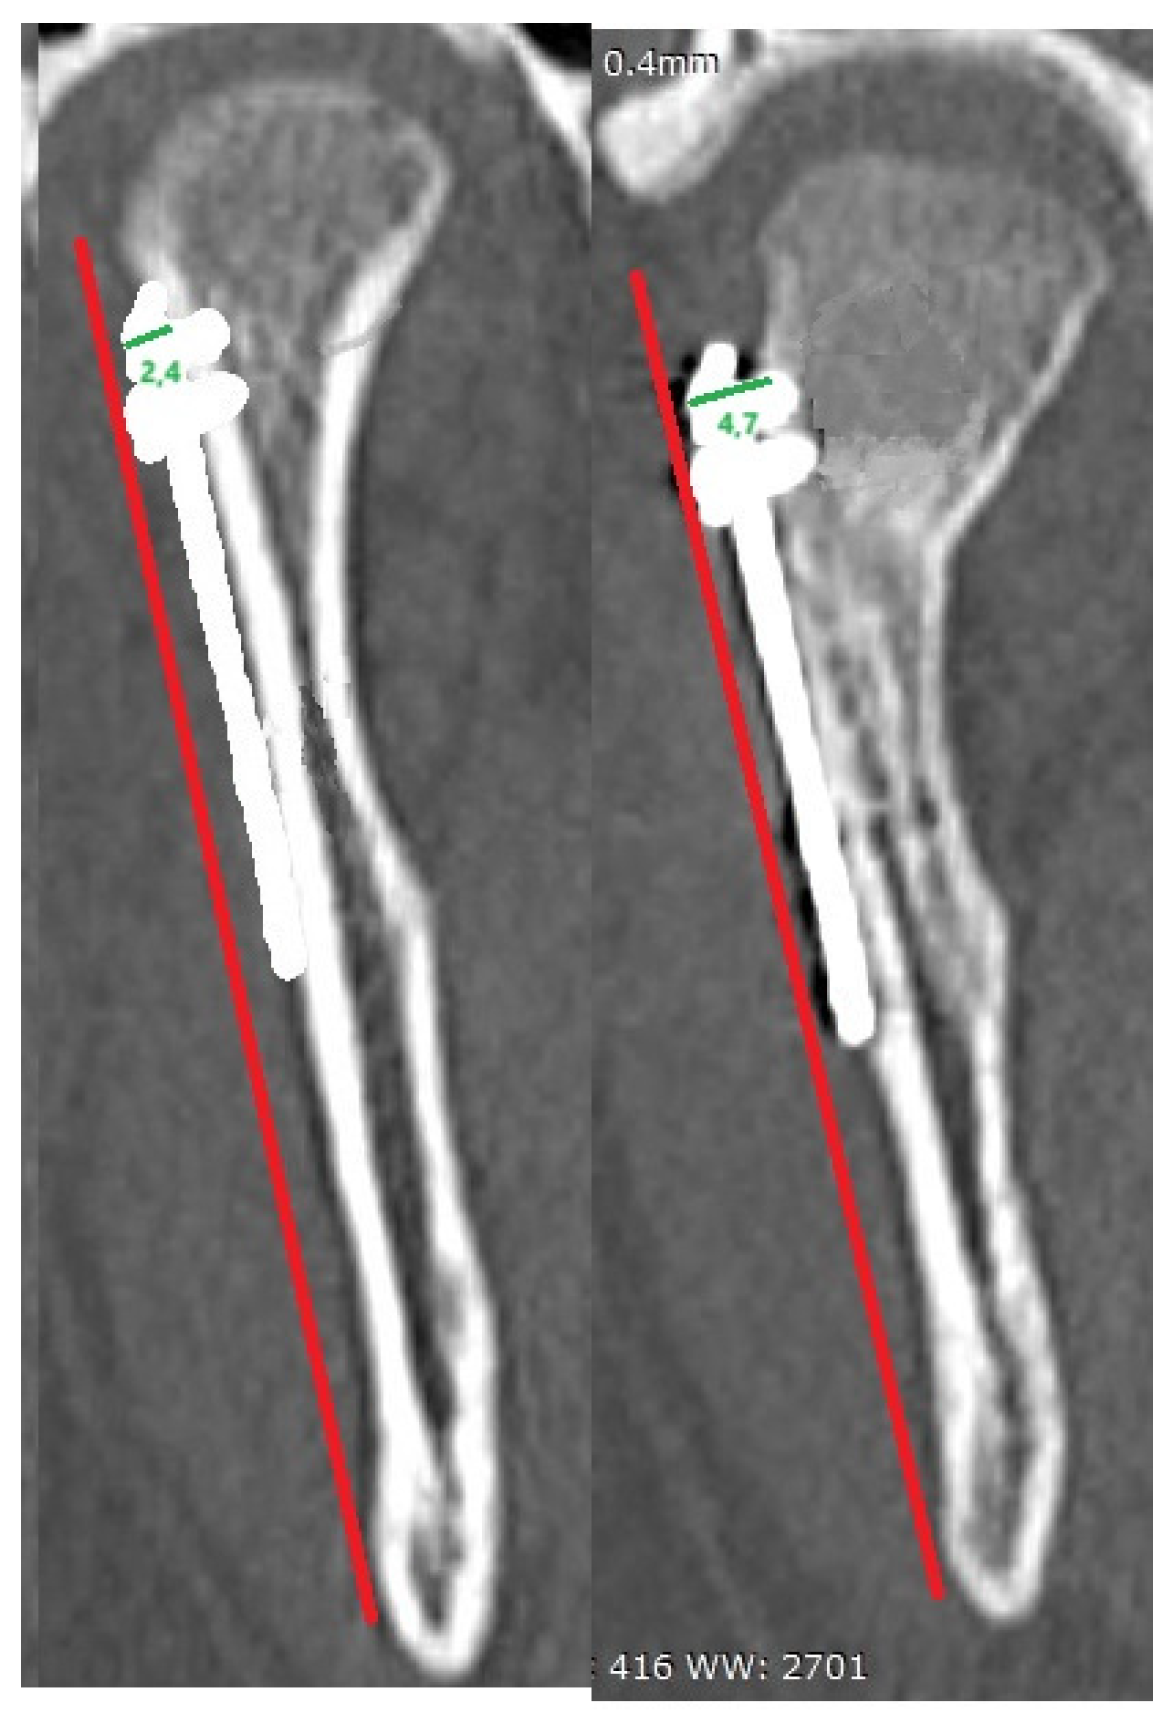

Effect of the distance from the plate edge to the lateral pole of the mandibular head (in mm) is presented in

Figure 4. The recorded values ranged from those overlapping with the lateral pole (negative values) to a distance of as much as 20 mm. A statistical evaluation indicated that proximity to the lateral pole is a risk factor (p < 0.05) for bone resorption at the plate edge (

Figure 5).

It should be noted (

Figure 4) that the location of osteosynthesis is related to resorption. Based on our findings, factors that induce resorption are not limited to insertion of a plate on the articular surface or covering the lateral pole of the mandibular head. Even lower osteosyntheses within the mandibular neck entail resorption. Only distant placement of the fixation material, more than 14 mm away from the lateral pole, does not lead to bone resorption at the osteosynthesis site. This is probably the result not only of irritation of the surrounding tissues with titanium material [

19,

It is worth noting when entering the surgery, choosing a preauricular approach, it is worth to be tempted to extend retromandibularly, When treating the fracture, an appropriate distance should be selected - 14 mm below the lateral pole. This is because, as seen in [

Figure 4], this can result in bone loss both around the screw head and at the lateral pole. This will help choose the proper length and shape of the ORIF plate. Next, that the optimal number of screws is 9, and during the procedure, supplying lower fractures of the mandibular condylar processes, there is no need to take into account the length of the screws.